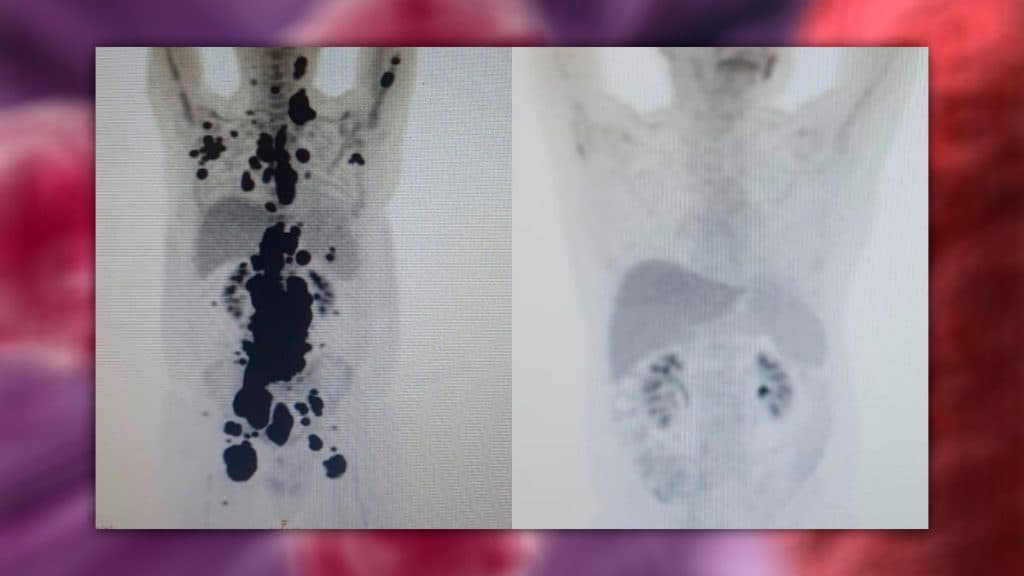

Tomografias de Paulo Peregrino antes e depois do tratamento com CAR-T Cell (Imagem: Arquivo pessoal)

As duas imagens acima, do Pet Scan (tomografia feita com um contraste especial), representam “dois Paulos”. A da esquerda, o paciente que tinha como caminho único os cuidados paliativos, quando a alternativa é dar conforto, mas já sem expectativa de cura. E a da direita, um paciente com um organismo já sem tumores após o tratamento com CAR-T Cell.